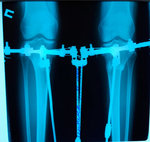

Пациентка - 30 лет.

Дата операции - 04.04.2019г.